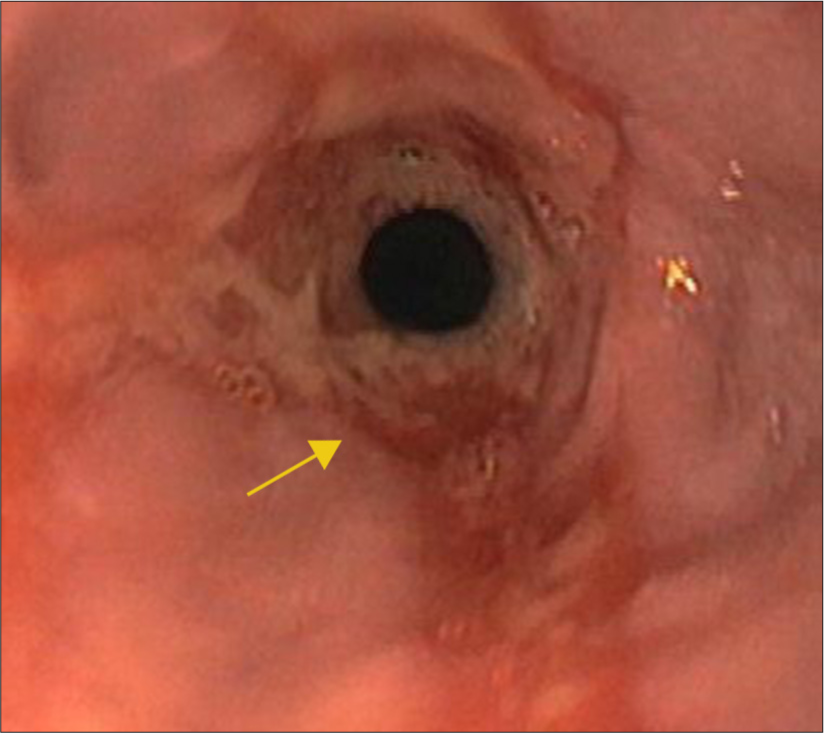

Figure 4 shows pre management endoscopy image at the site of stricture showing ulcerated mucosa.

- Pre-management endoscopy image confirming stricture with ulcerated mucosa denoted by yellow arrow.